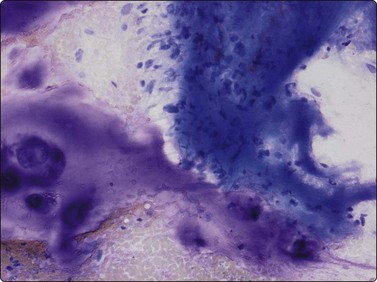

The characteristic findings are the abundant background of myxoid ground substance and the large, physaliphorous cells with abundant pale, vacuolated, bubbly cytoplasm and well-defined cell borders. The myxoid matrix, often fibrillar, intensely purple in MGG smears, pale pink in H&E, forms a network encircling individual tumor cells, cell clusters or fragments (Fig. 16.28). The physaliphorous cells have one, sometimes two, rounded nuclei of moderate size, a bland chromatin and small nucleoli. Moderate anisokaryosis is common (Fig. 16.29A). Some tumors show clusters of markedly pleomorphic cells with prominent nucleoli, and multinucleated tumor giant cells may be present (Fig. 16.29B). There are also clusters of small to medium-sized, non-characteristic or epithelial-like cells with rounded nuclei. The cytoplasm of these cells may be vacuolated; some cells have one large vacuole pushing the nucleus to the periphery and may resemble signet ring cells (Fig. 16.30A). The main differential diagnosis is chondrosarcoma. If only wet-fixed smears are available, metastatic clear cell carcinoma, especially renal cell carcinoma or mucus-producing adenocarcinoma can also cause differential diagnostic difficulties. The abundant ground substance may be inconspicuous in H&E or Pap smears and the epithelial-like tumor cells may give a false impression of an epithelial neoplasm (Fig. 16.30B). Typical physaliphorous cells are never encountered in chondrosarcoma and the network of myxoid matrix encircling individual cells is not a feature of either chondrosarcoma or metastatic carcinoma. A chordoma originating in the cervical spine does not always present as a midline tumor and, if information on the radiologic finding is not available, may be interpreted as a malignant myxoid soft tissue tumor. Chordomas typically express S-100 protein and low molecular weight cytokeratins. The cytological appearance of chordoma in FNB has been evaluated in rather large series.37-39

image image

Fig. 16.29 Chordoma

(A) Moderate anisokaryosis is a common feature of smears from chordoma (H&E, IP); (B) Markedly pleomorphic cells with prominent nucleoli, and multinucleated tumor giant cells may be present (MGG, HP).